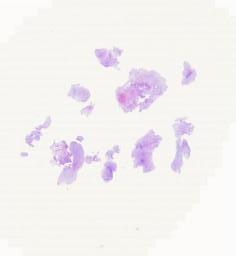

临床资料: 男性,21岁,发作性四肢抽搐伴意识障碍14个月余 头颅CT及MRI:头部CT示右颞顶叶小片状稍低密度影,边缘模糊,内见斑片状钙化影,考虑为右颞顶叶占位,建议MRI检查。MRI示右颞枕叶底面内侧可见片状不均匀长T1长T2信号影,Flair可见稍高信号。DWI可见不均匀小片状稍高信号。增强后,右颞枕叶内侧病变可见片状不均匀强化影,病变边界不清。PWI:右颞枕叶内侧病变区CBF、CBV灌注稍增高。MRS:右颞枕叶病变NAA峰明显减低,Cho峰明显增高,可见脂质乳酸峰。影像学诊断:右颞枕叶内侧占位,考虑为胶质瘤可能性大。 术中所见:术中见肿瘤位于右颞枕,大小约3.8×2.6×1.8cm,呈灰白色,质韧,血供一般,边界不清。肿瘤向下方达中颅窝底,并突入侧脑室三角区内生长。

大体所见: 灰白、灰褐破碎组织一堆,切面灰白、灰褐质软,总大小4.5x4.5x2.7cm。